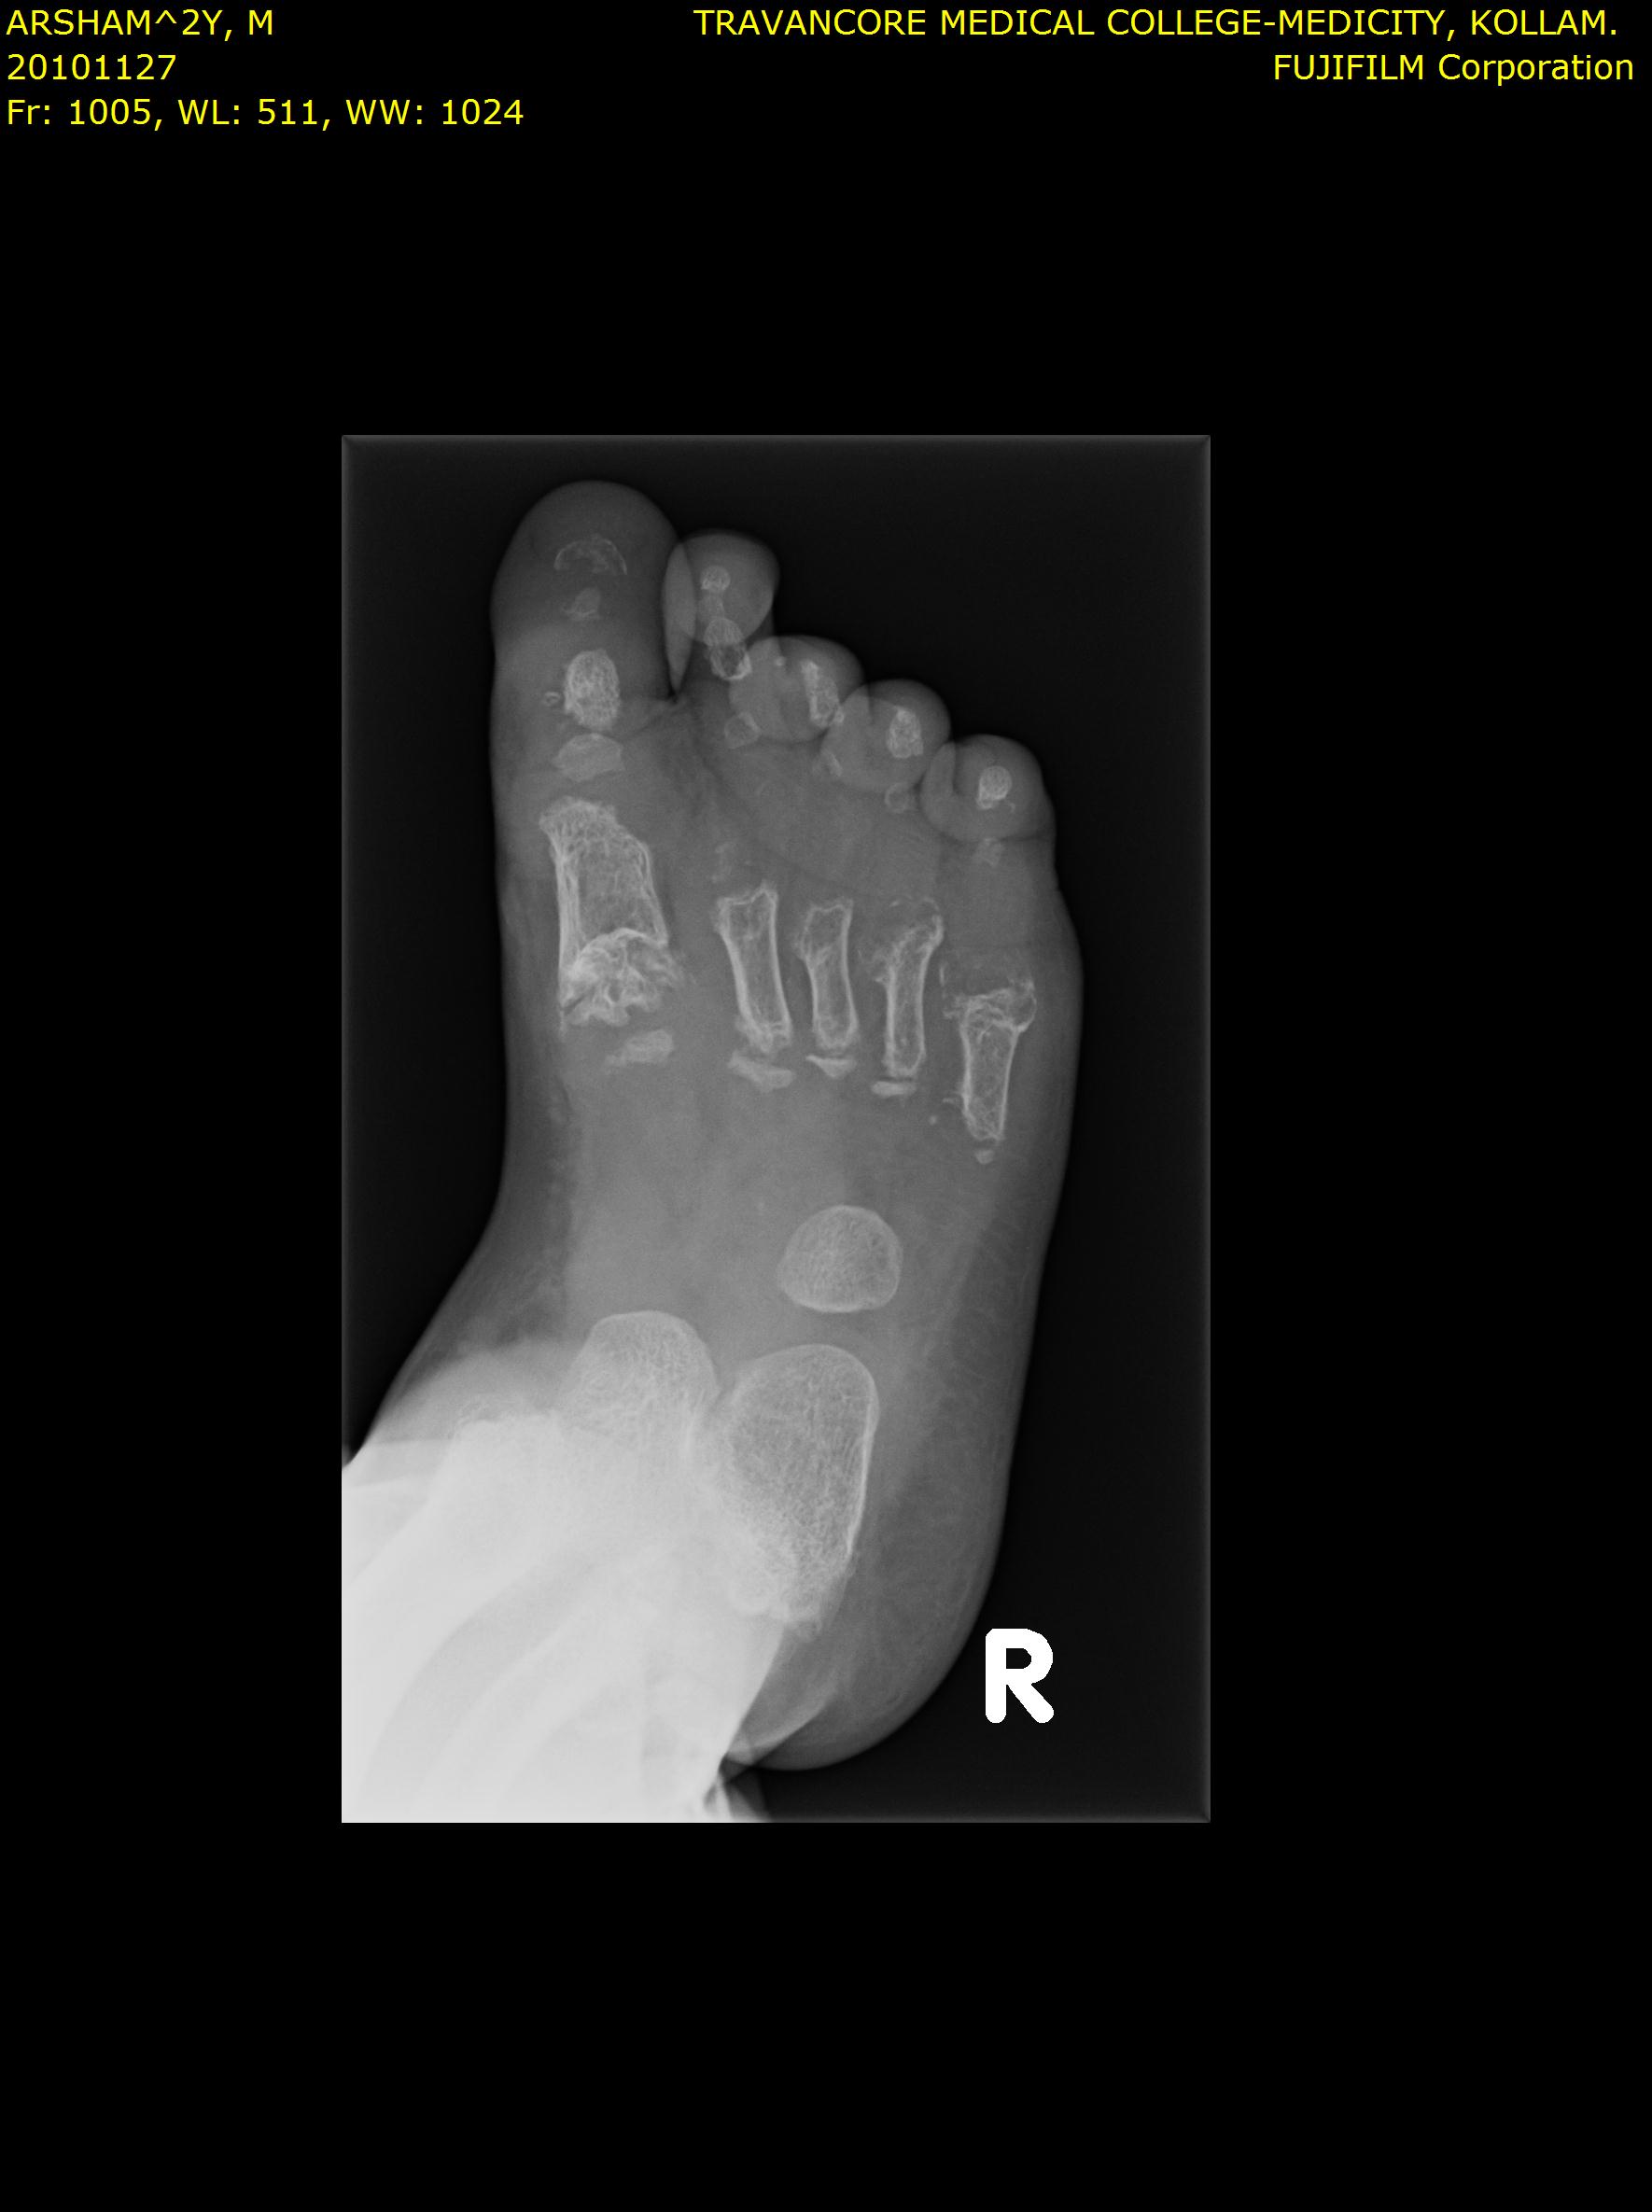

Here we share radiographic images to help with diagnosis of Jansen's disease:

Jansen's patients show extreme disorganization of the metaphyses of the long bones and of the metacarpal and metatarsal bones in sharp contrast to the almost normal appearance of the epiphyseal centers, which on x-ray appear widely separated from the long bones. The chin is receding. The fingers, especially the distal phalanges, are very short. The spine, pelvis, and lower legs are distorted.